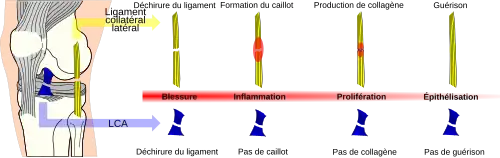

Perspectives thérapeutiques

Contrairement aux ligaments collatéraux, les LC ne sont rarement capables de se cicatriser spontanément par une mise au repos après une rupture. Pour une rupture de ligament collatéral tibial, par exemple, il suffit d'un bandage qui doit être porté environ six semaines, pour que les deux bouts puissent se rejoindre et cicatriser, et ainsi guérir la rupture. La cause de cette situation n'est pas bien connue. Plusieurs facteurs sont en discussion : peut-être le liquide synovial qui baigne les LC empêche-t-il cette guérison[291],[292] ; les échanges de collagène après la blessure pourraient être modifiés après la blessure[293],[294] ; ou des déficits intrinsèques tels que l'expression des gènes des cellules formant les LC pourraient être responsables de l'effet[295],[296],[297],[298],[299],[300],[301].